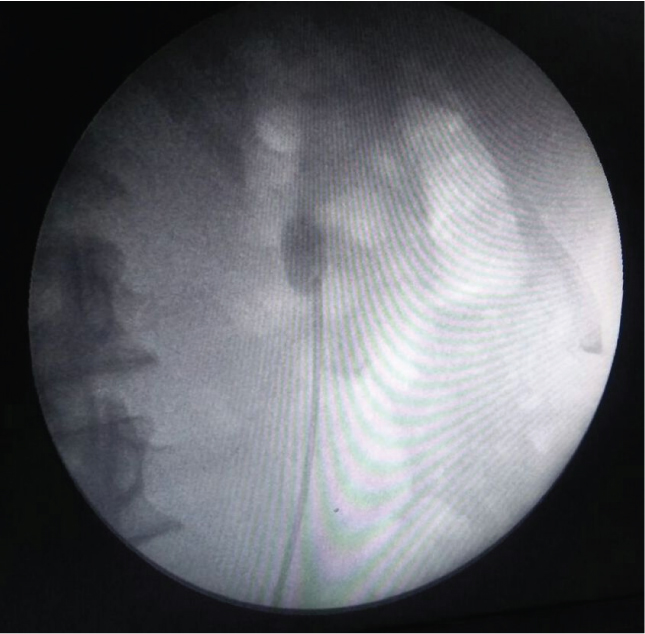

In Group-I (antegrade air pyelogram), the collecting system was delineated by targeting the renal stone using a 22 gauge spinal needle under fluoroscopic guidance while the patients were in the prone position [Table/Fig-1a-c]. A 22 gauge spinal needle was positioned at 0/30-degree by rotating C-arm enabling the urologist to aspirate urine from the collecting system hence confirming the proper positioning. Then the air pyelogram was performed using air. Following this the targeted calyx was punctured with 18 gauge diamond tip initial puncture needle and 0.038 inch J-tip PTFE guide wire put. Whereas, in Group-II (retrograde air pyelogram) urethral catheter was inserted in lithotomy position and then patient was turned from the lithotomy to prone position. Room air was injected through ureteric catheter for PCS identification [Table/Fig-2]. Targeted calyx was identified and access was attempted under fluoroscopic guidance with 18 gauge diamond tip initial puncture needle and J-tip guide wire put. Subsequent tract dilatation and stone extraction were same in both groups. Assessment of following parameters was made:

Retrograde air pyelogram using ureteric catheter.